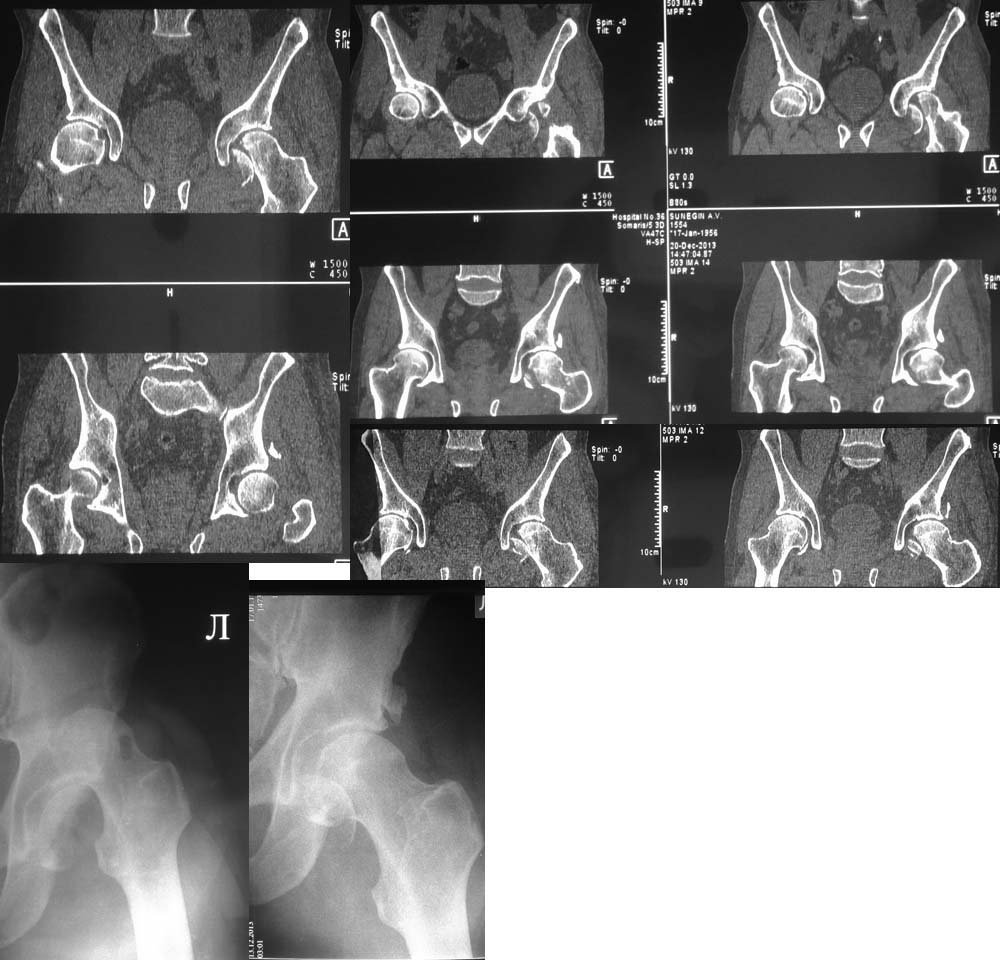

Поскольку имеется перелом края вертлужной впадины, перелом относится к типу Pipkin IV. Ну, это так, к слову. Больной до шестидесяти лет, поэтому методом выбора должна быть открытая репозиция перелома, остеосинтез винтами. Головки винтов должны быть заглублены ниже уровня суставного хряща. Нет на представленной КТ срезов в корональной плоскости, поэтому невозможно точно определить имеющийся дефект задневерхнего края вертлужной впадины и, следовательно, необходимость репозиции и фиксации её отломанного фрагмента. Лучшим доступом в данном случае является латеральный доступ с отсечением большого вертела по Ganz с вывихом головки бедренной кости в рану. Доступ позволяет не только без проблем выполнить репозицию и фиксацию не только перелома головки бедренной кости, но и края вертлужной впадины в случае необходимости. Доступ подробно описан в «Rockwood And Green's Fractures In Adults».

Один случай из личного опыта, когда использовался этот доступ – во вложенном файле.